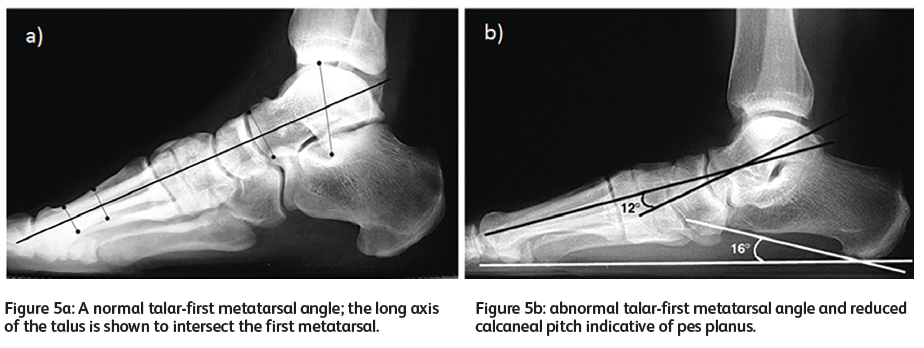

엄지의 MP joint와 navicular bone(주상골)의 결절, 발 안쪽 복사뼈를 잇는 선(제1중족골 축) 과 거골(tarus)의 중간 축(거골축)이 이루는 교차각을 측정해보면 정상인 경우 일직선이고 평발인 경우 거골축이 제1중족골축의 바닥쪽을 향해 내려간다.

정상범위는 각도가 발바닥 혹은 발등쪽으로 4도이하일 경우이고, 만약 반대로 발등쪽으로 향하면 아치가 높은 요족이다. 그외 lateral view에서 calcaneal pitch (종골고)와 바닥이 이루는 각도 또한 줄어든다.